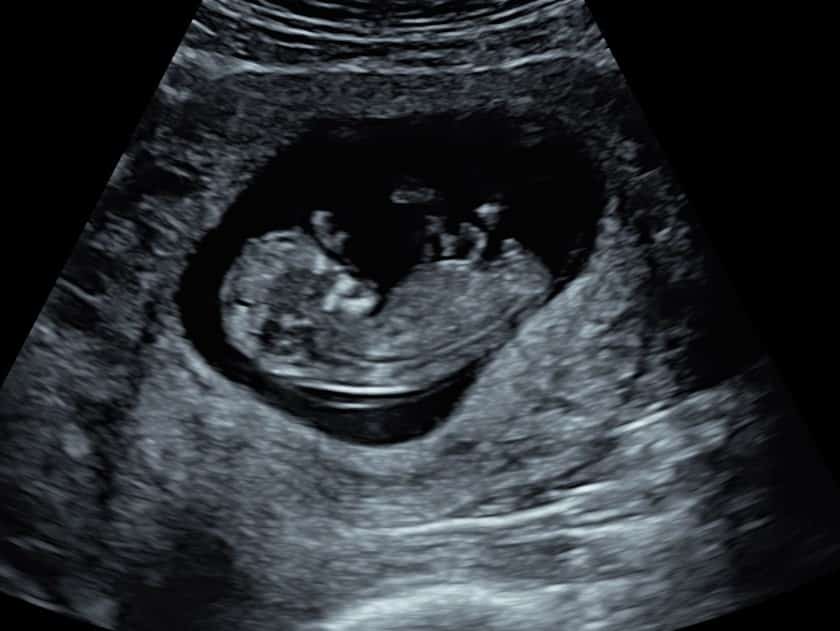

The first thing the sonographer looks for is the position of baby. They will check the baby is in the uterus as it should be, rather than elsewhere which can be dangerous for mum. The sonographer will then look for the number of pregnancy sacs and babies to confirm a single or multiple pregnancy. The heartbeat is next; during your early pregnancy scan we do not listen to the heartbeat as it wouldn’t be safe for baby, but we will show you the heartbeat flickering on our screens.

Once the heartbeat is confirmed, the sonographer will check the pelvic area and ovaries to make sure the area around baby is healthy. If you’re experiencing any worrying symptoms, our sonographer will be able to confirm the reasons why during this part of the scan.

Once the pelvic assessment is complete, the sonographer will return to your baby and measure their length from crown to rump (head to tail) to provide you with accurate dating.